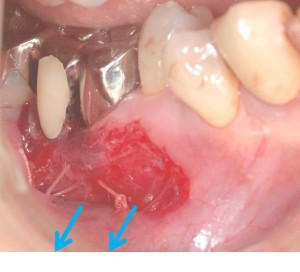

そこで、歯周外科処置によって、動く歯茎を下方向に移動しました。

そして、上顎の裏側より、「動かない歯茎」を移植しました。